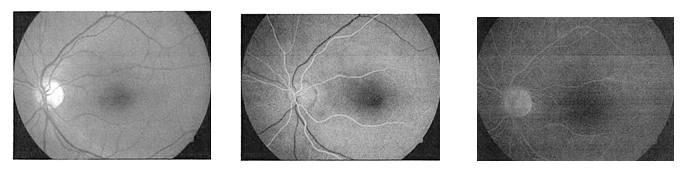

Angiografia fiuoresceinowa to badanie polegające na wykonaniu serii fotografii dna oka (opcjonalnie tęczówki) po uprzedniej, dożylnej aplikacji fluoresceiny, czyli specjalnego środka cieniującego/fluoryzującego.

Badanie pozwala na wyraźne dostrzeżenie krążenia krwi w naczyniach żylnych i tętniczych siatkówki gałki ocznej oraz umożliwia dokonanie obiektywnej oceny stanu nabłonka barwnikowego siatkówki.